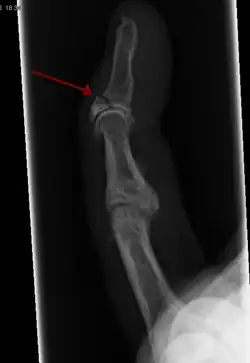

A bone fracture (abbreviated FRX or Fx, Fx, or #) is a medical condition in which there is a partial or complete break in the continuity of any bone in the body. In more severe cases, the bone may be broken into several fragments, known as a comminuted fracture.[1] An open fracture (or compound fracture) is a bone fracture where the broken bone breaks through the skin.[2]

- Broken finger – a fracture of the carpal phalanges